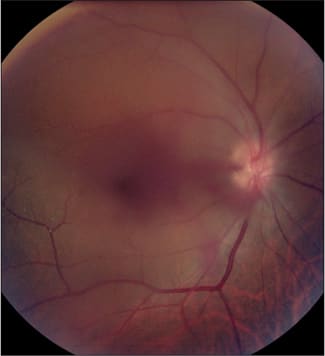

On examination, his corrected visual acuity was 20/70 in the right eye and 20/40 in the left. The anterior segment was benign with the exception of bilateral 1-2+ nuclear sclerotic cataract. The right eye had vitreous hemorrhage with a few tiny white crystals visible in the inferotemporal macula (Figure 1). Similarly, the fellow eye had white crystalline deposits scattered throughout the macula; the majority were located within the macular capillary network (Figure 2). On fluorescein angiography there was bilateral peripheral non-perfusion with adjacent late leakage of dye, which correlated with small fronds of retinal neovascularization evident on clinical examination (Figures 3 to 6).

Figure 2. White, crystalline intravascular talc deposits throughout the macula, left eye.